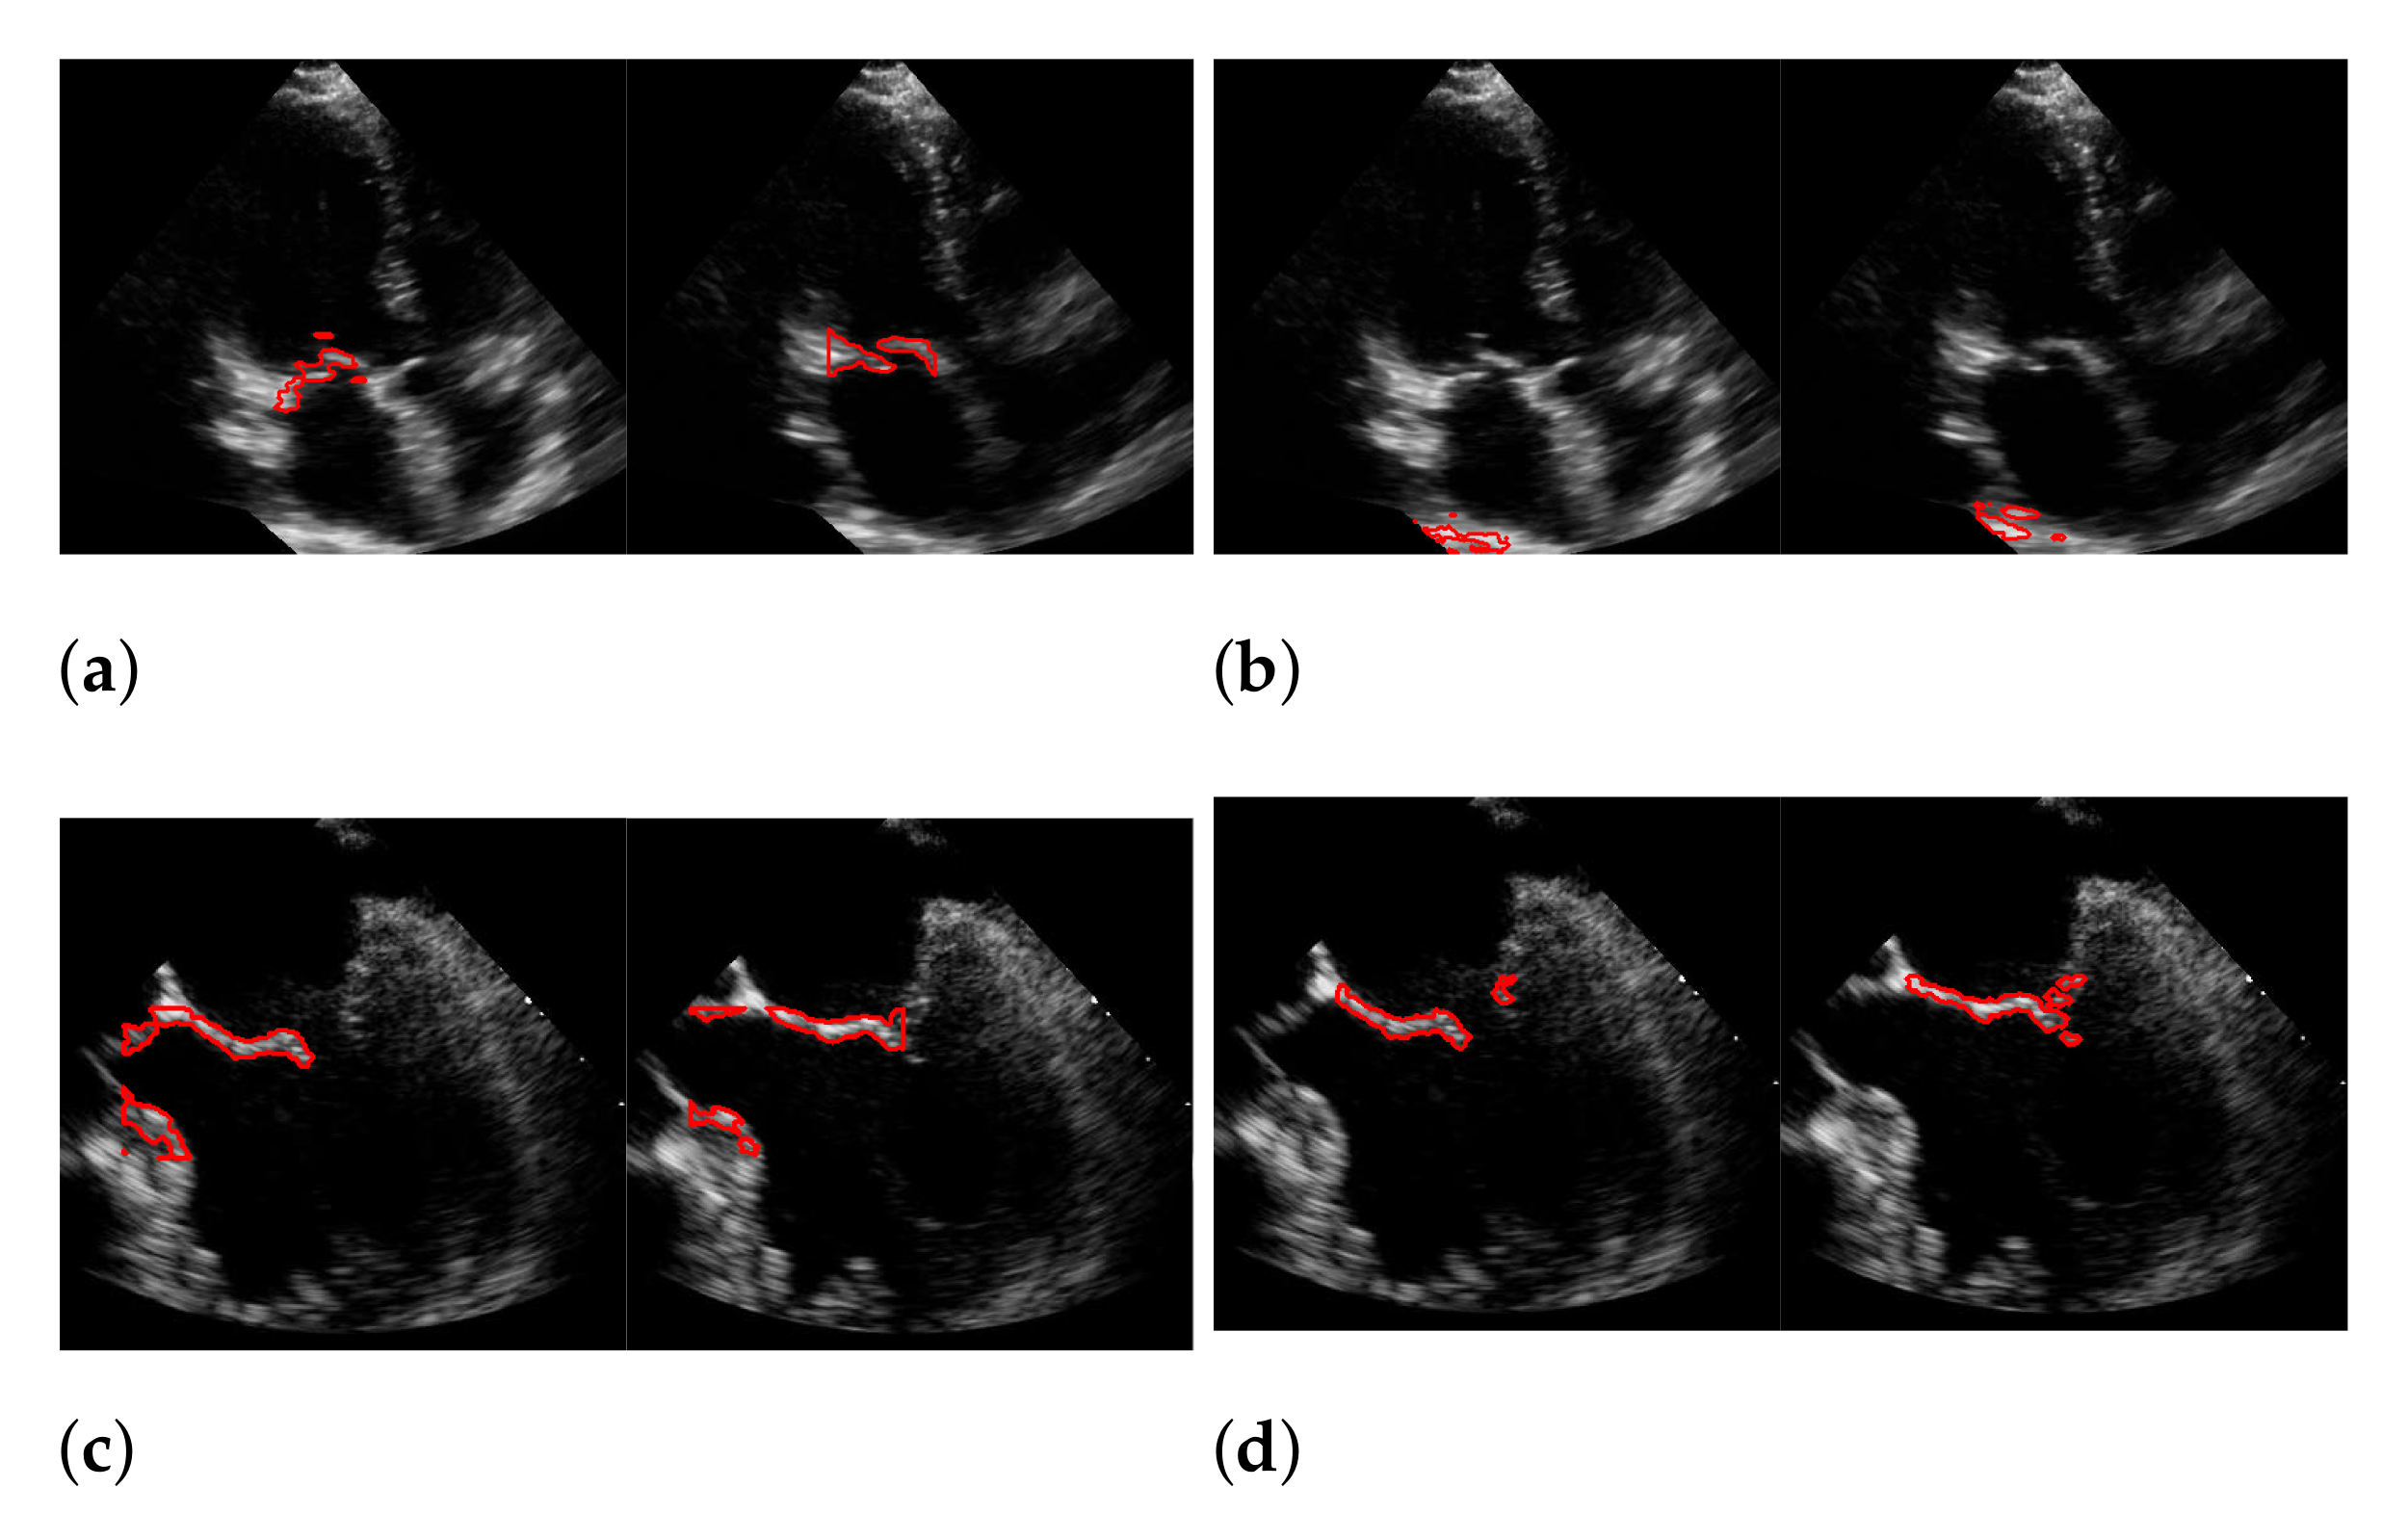

Figure 18.

Segmentation in the cases of the largest differences between the f1-scores of our approach (segmentation with windowing) (a,c) and the one of Corinzia et al. (b,d). The results in (a,b) belong to the red rightmost bar of Figure 15, the results in (c,d) belong to the leftmost bar.

In both figures (Figure 16 and Figure 18), the upper row of the segmentation by [9,40] gives an example of a missed mitral valve using a windowing technique and underlines the importance of correct valve detection. The upper row videos are especially challenging because of a partly disappearing mitral valve and weak contrast.